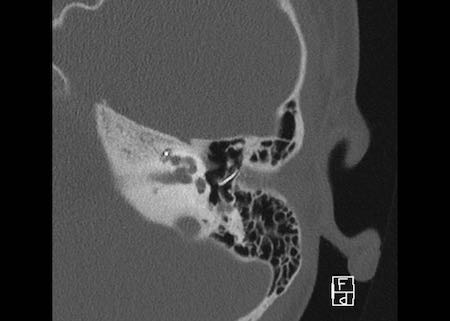

Bên trái là hình ảnh của một bé gái 2 tuổi.

Các hình ảnh từ kết quả chụp CT được thực hiện trước khi cấy ốc tai điện tử.

Quan sát thấy dị dạng nhẹ ở đỉnh ốc tai – không có sự phân tách giữa vòng thứ hai và vòng thứ ba, và trụ ốc tai xương vắng mặt.

Cống tiền đình bình thường.